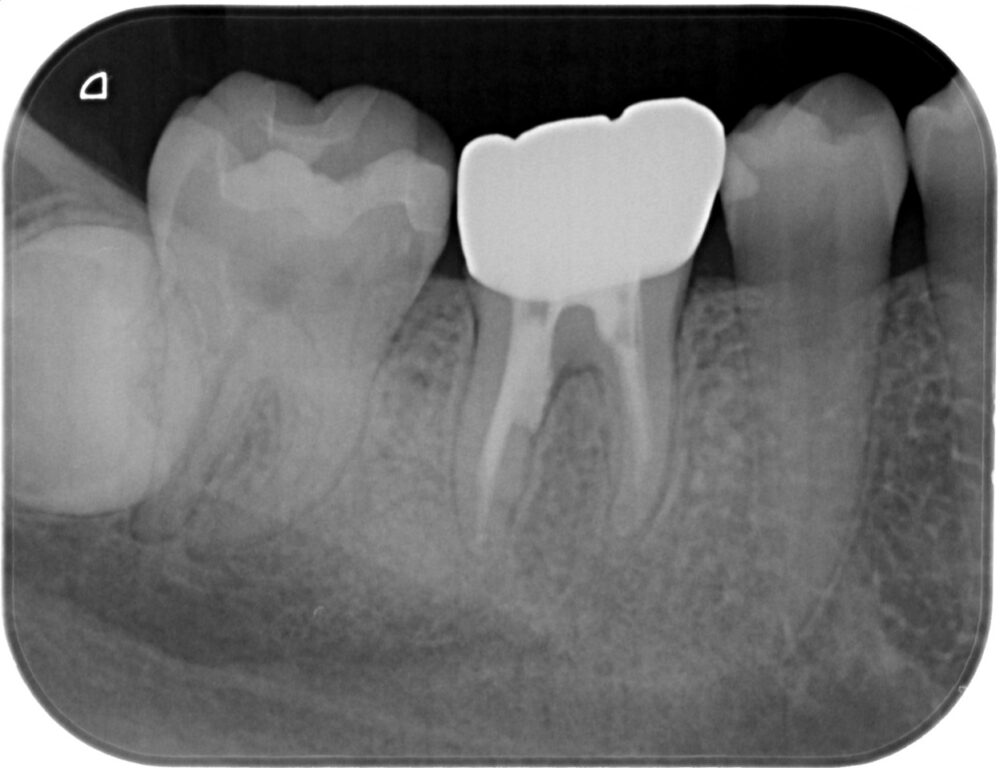

症例1:パーフォレーションリペア症例

(歯の中に大きな穴が空いてしまっているのを埋めて再生を促す治療)

AFTER |

| 医院の診断 | 虫歯の再発、慢性根尖性歯周炎、遠心根人為的穿孔 |

人為的根穿孔を起こした部分に感染を起こしており、歯周ポケットが9㎜ありました。 ラバーダム防湿とマイクロスコープを使用して丁寧に治療を行いました。 殺菌性があり歯を補強することのできるMTAという根管充填材料を使用して、歯周ポケットは2㎜に改善しました。 |